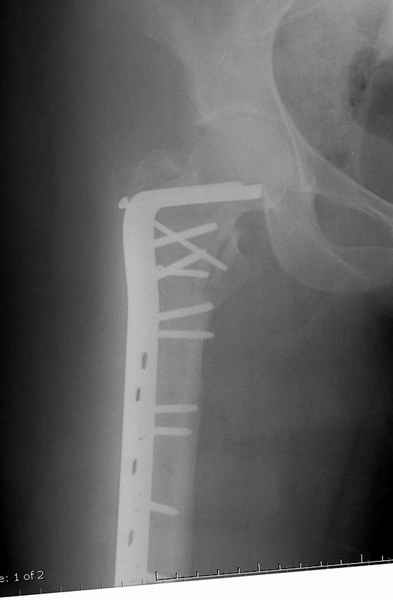

Вот пример наших американских коллег про DHS. Видно, как стелескопировались отломки, хотя поначалу был оставлен диастаз.

Фиксатор или DHS 130 градусов или PFN с короткой ножкой. Если DHS, то шуруп должен находиться в центре шейки и дополнительно еще простой длинный шуруп против ротации в проксимальной части шейки над шурупом DHS. Полную нагрузку на ногу начать через 6 недель.

Большие преимущества у интрамедуллярных штифтов, метод хорош и можно произвести из минимального доступа, но во время операции необходимо контролирование варуса, затем приступить к блокированию.